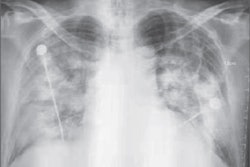

Acute severe hypoxemic respiratory failure was prominent, and all patients required invasive mechanical ventilation. Before intubation, five patients had received a failed trial of noninvasive positive-pressure ventilation. Chest radiography at the time of intubation showed airspace changes ranging from unilateral lobar to bilateral diffuse movement, and chest CT performed in three patients confirmed the same patterns.

"Chest x-ray is needed for the initial evaluation and in the follow-up of critically ill patients with MERS-CoV," Arabi said in an interview with AuntMinnie.com. "It shows unilateral or bilateral infiltrates."